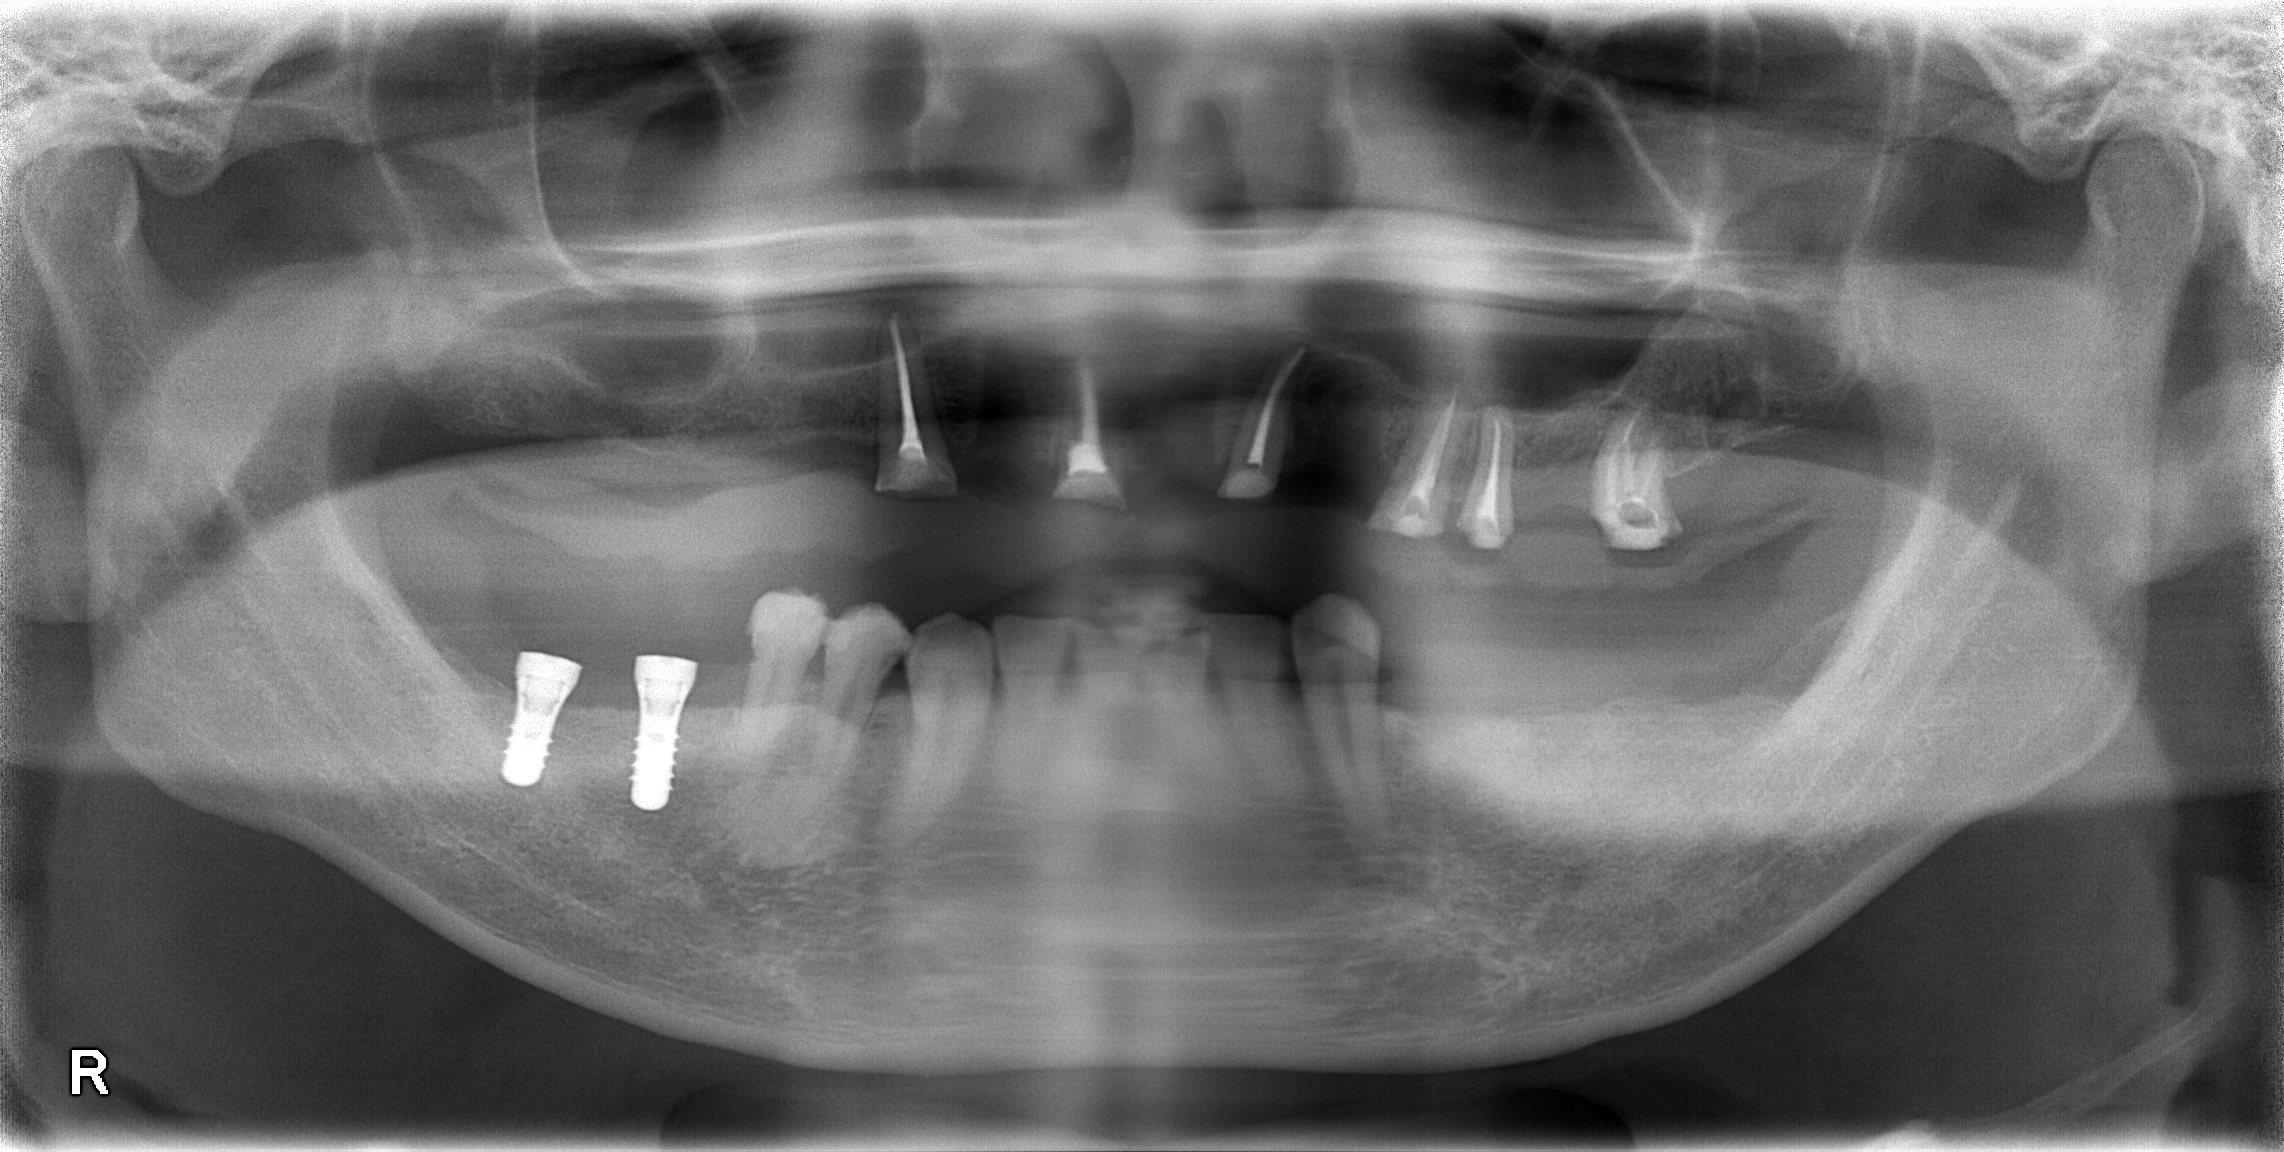

インプラント

重度虫歯からのインプラント・入れ歯治療(*^-^*)